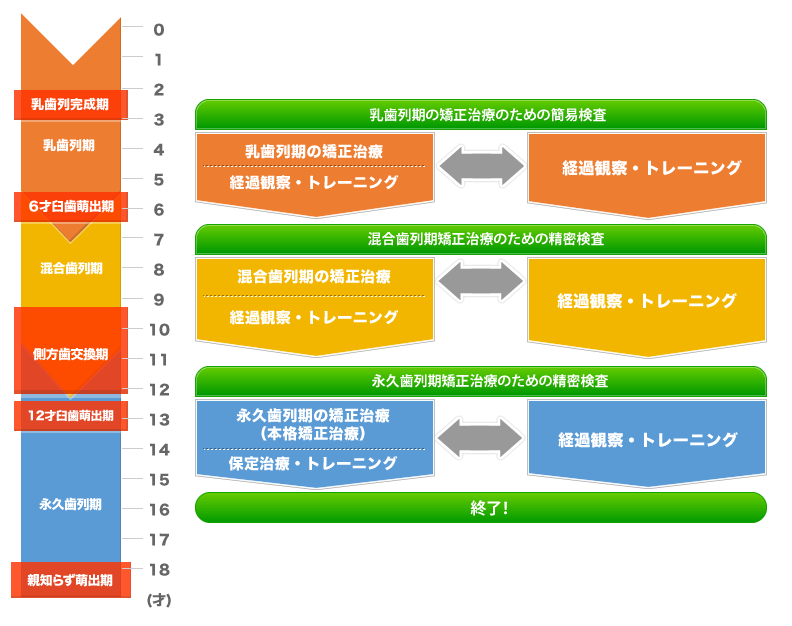

症例によっては治療を開始するまで数か月おきに経過観察・歯みがき指導・習癖等のトレーニングを行います。